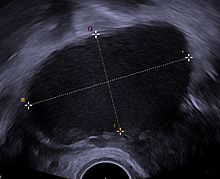

Transvaginal ultrasonography showing a 67 x 40 mm endometrioma as distinguished from other types of ovarian cysts by a somewhat grainy and not completely anechoic content.

Ultrasound

The use of pelvic ultrasound may identify large endometriotic cysts (called endometriomas). However, smaller endometriosis implants cannot be visualized with ultrasound technique.[90]

Vaginal ultrasound has a clinical value in the diagnosis of endometrioma and before operating for deep endometriosis.[91] This applies to the identification of the spread of disease in individuals with well-established clinical suspicion of endometriosis.[91] Vaginal ultrasound is inexpensive, easily accessible, has no contraindications and requires no preparation.[91] Healthcare professionals conducting ultrasound examinations need to be experienced.[91] By extending the ultrasound assessment into the posterior and anterior pelvic compartments the sonographer is able to evaluate structural mobility and look for deep infiltrating endometriotic nodules noting the size, location and distance from the anus if applicable.[92] An improvement in sonographic detection of deep infiltrating endometriosis will not only reduce the number of diagnostic laparoscopies, it will guide management and enhance quality of life.[92]